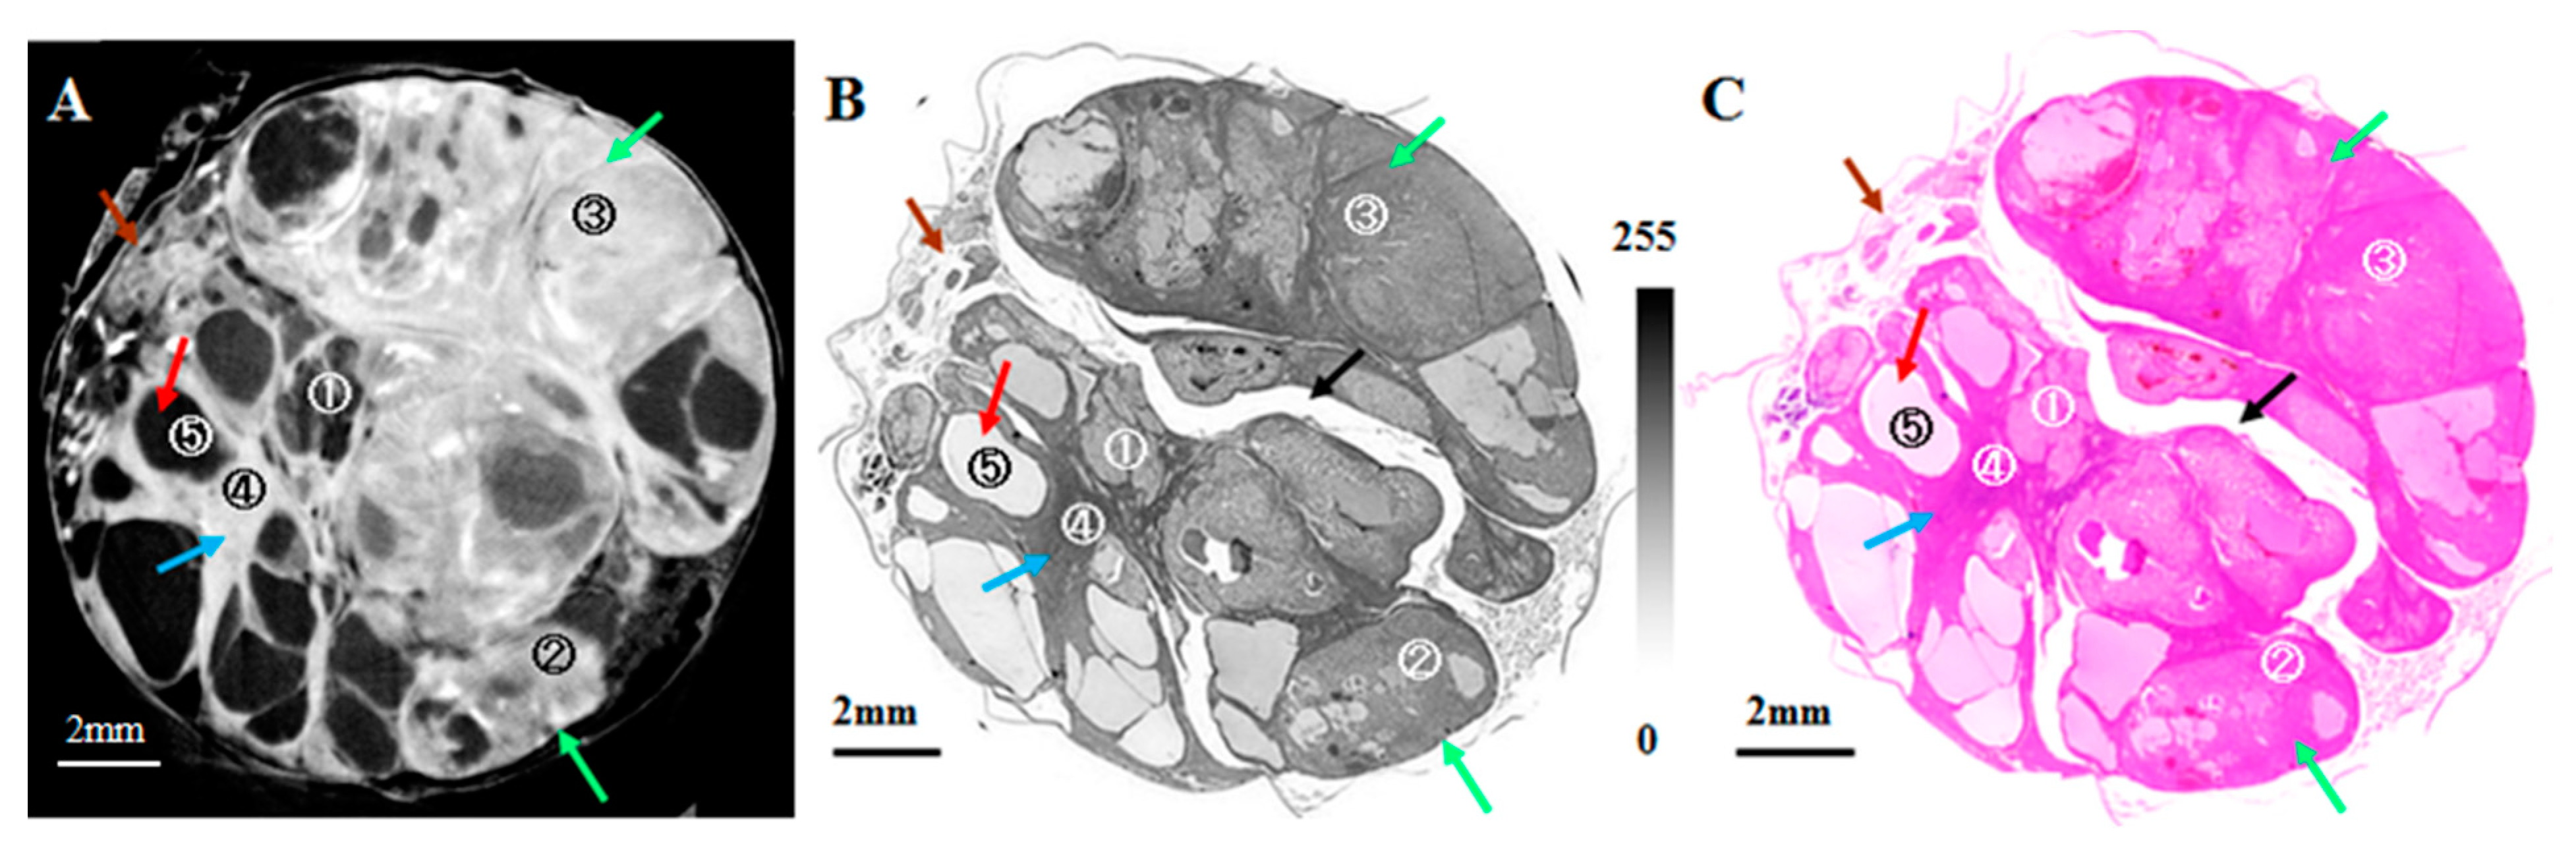

- Thet Thet, L.; Yoneyama, A.; Imai, M.; Maruyama, H.; Hyodo, K.; Takeda, T. Testicular seminoma in the aged rat visualized by phase-contrast X-ray computed tomography. Acta Radiol. Open 2018, 7, 205846011880665. [Google Scholar] [CrossRef] [Green Version]

- Lwin, T.T.; Yoneyama, A.; Maruyama, H.; Takeda, T. Visualization Ability of Phase-Contrast Synchrotron-Based X-ray Imaging Using an X-ray Interferometer in Soft Tissue Tumors. Technol. Cancer Res. Treat. 2021, 20, 15330338211010121. [Google Scholar] [CrossRef]